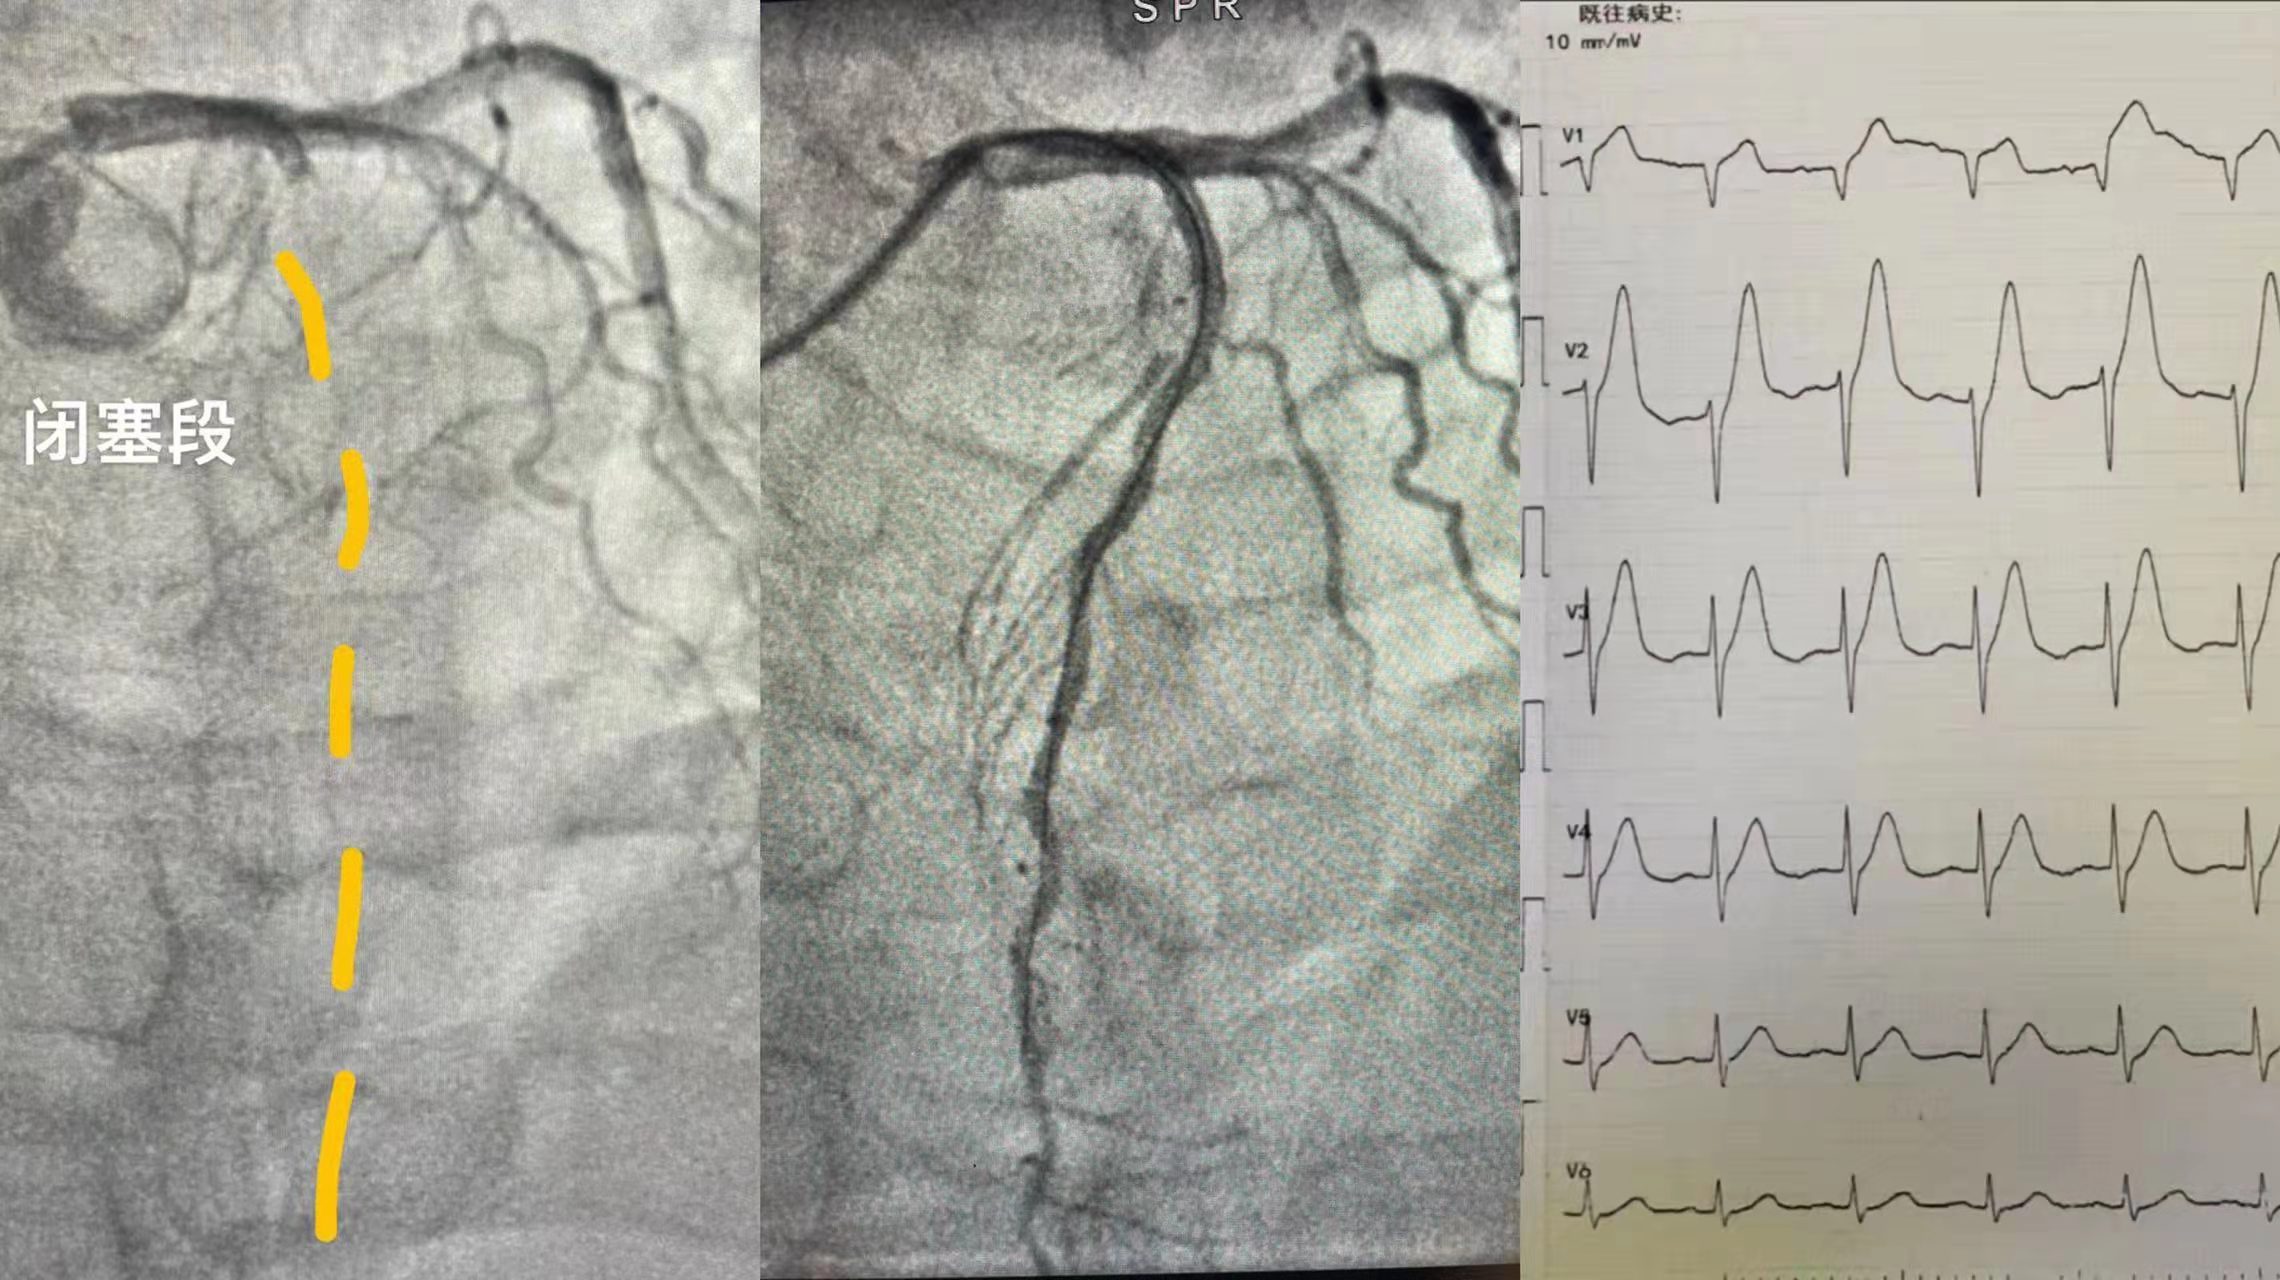

7月(yuè)(yuè)26日晚,心病科7台手術後,還沒有吃飯,來(lái)急診突發心梗,入院5分(fēn)鍾心髒驟停,此病人(rén)急診室顫,除顫後立即入導管室行介入手術,入導管室後6分(fēn)鍾即完成造影,确認罪犯血管,11分(fēn)鍾恢複閉塞段血流,術中病人(rén)再次室顫, 搶救成功,45分(fēn)鍾完成全部手術,術後病人(rén)生(shēng)命體(tǐ)征平穩,入重症監護室觀察治療,這(zhè)一(yī)切都得益于團隊高速、高效運轉和所有默默付出的中醫(yī)院人(rén).